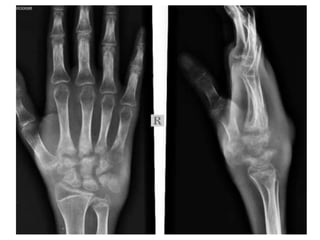

Hand and Wrist

Appearance(Years)

• 1st – lower end radius, capitate,

hamate

• 2nd – Head of 2,3,4,5th

metacarpal, bases of proximal

phalanges

• 3rd – Triquetral, base of first

metacarpal, middle and

terminal phalanges

• 4th – lunate

• 5th – trapezium,trapezoid,

scaphoid

• 6th – lower end of ulna

• 12th- Pisiform

Fusion(Years)

• 17th – base of first

metacarpal

• 18th – epiphysis of

metacarpals, phalanges

and lower end of ulna

• 19th – lower end of

radius

Ossification

• Depiction of the order of appearance of the

individual carpal bones. The usual sequence is:

capitate (1), hamate (2), triquetral (3), lunate (4),

• trapezium (5), trapezoid (6),

• navicular or scaphoid (7) and

• pisiform (8).

• The distal epiphysis of the radius ossifies before the

triquetum and that of the ulna before the pisiform